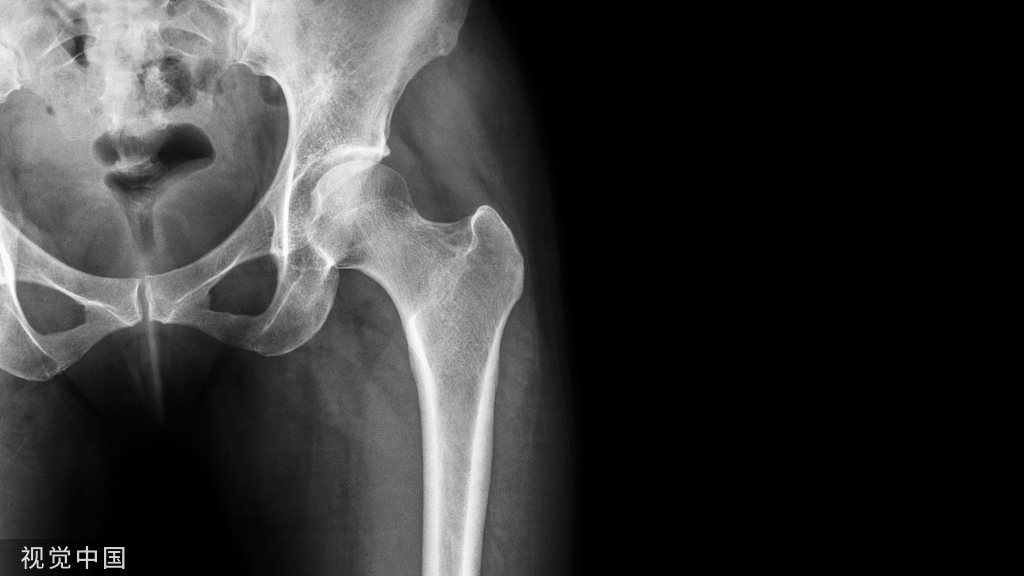

Poller钉及髓内钉置入操作方法分为六步:1.沿移位骨块(远干骺端为远端骨块、近干骺端为近端骨块)作一中轴线;

图1股骨远端骨折示例。沿股骨远端骨块作一中轴线,骨折线与中轴线相交,形成2锐角(Acute angles)。